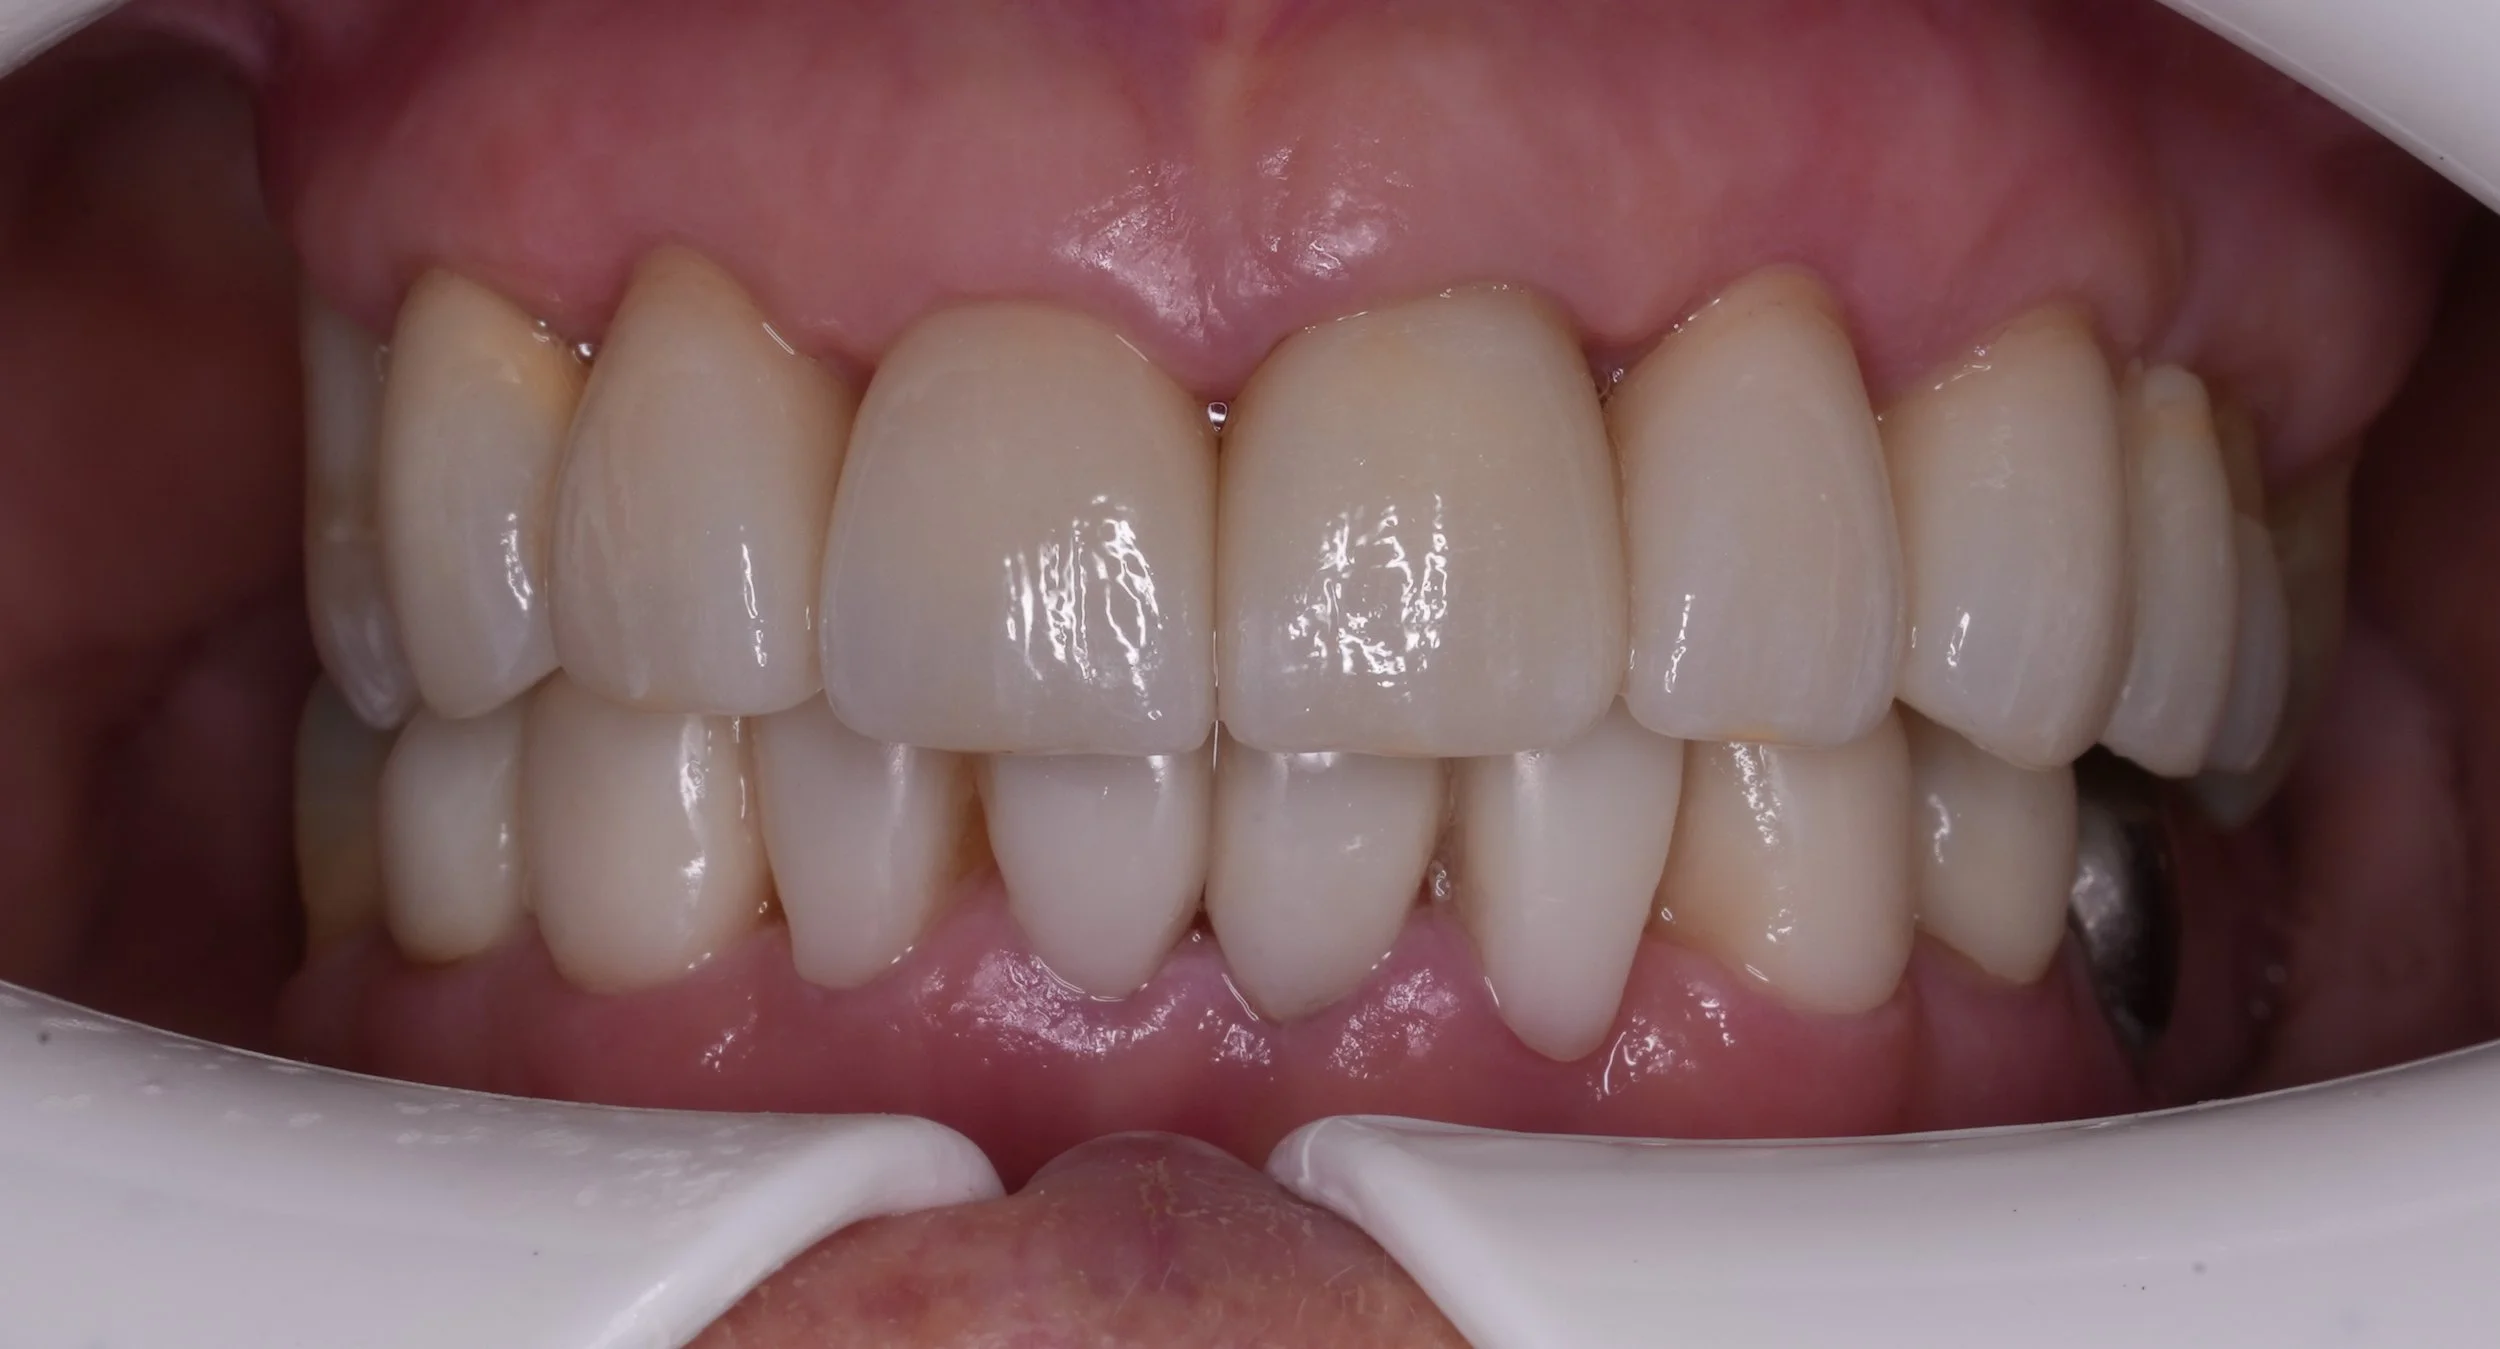

Fixed pros